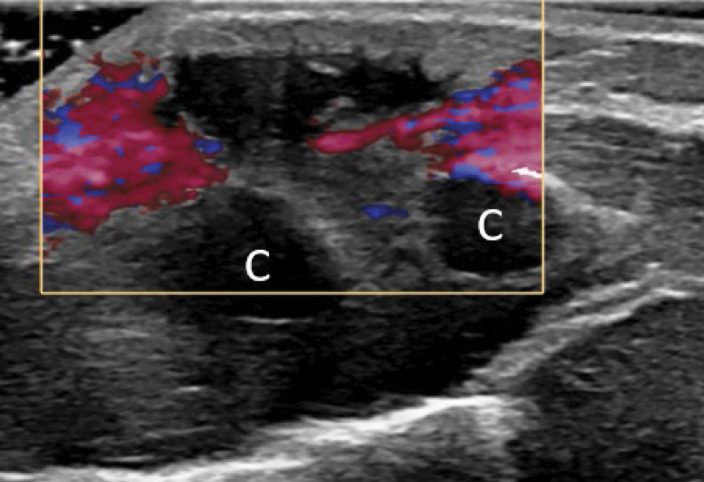

教学点:在血液结果正常且胸骨肿胀迅速增长且无创伤和全身性炎症疾病的婴儿中建立对儿童期自限性胸骨肿瘤(SELSTOC)的认识。

Teaching point: Creating awareness of self‑limiting sternal tumour of childhood (SELSTOC) in infants with rapidly growing sternal swelling with normal blood results and without trauma and systemic inflammatory diseases.